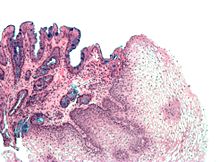

Both macroscopic (from endoscopy) and microscopic positive findings are required to make a diagnosis. Barrett's esophagus is marked by the presence of columnar epithelia in the lower esophagus, replacing the normal squamous cell epithelium—an example of metaplasia. The secretory columnar epithelium may be more able to withstand the erosive action of the gastric secretions; however, this metaplasia confers an increased risk of adenocarcinoma.[15]

The presence of goblet cells, called intestinal metaplasia, is necessary to make a diagnosis of Barrett's esophagus. This frequently occurs in the presence of other metaplastic columnar cells, but only the presence of goblet cells is diagnostic. The metaplasia is grossly visible through a gastroscope, but biopsy specimens must be examined under a microscope to determine whether cells are gastric or colonic in nature. Colonic metaplasia is usually identified by finding goblet cells in the epithelium and is necessary for the true diagnosis.[citation needed]

Many histologic mimics of Barrett's esophagus are known (i.e. goblet cells occurring in the transitional epithelium of normal esophageal submucosal gland ducts, "pseudogoblet cells" in which abundant foveolar [gastric] type mucin simulates the acid mucin true goblet cells). Assessment of relationship to submucosal glands and transitional-type epithelium with examination of multiple levels through the tissue may allow the pathologist to reliably distinguish between goblet cells of submucosal gland ducts and true Barrett's esophagus (specialized columnar metaplasia). The histochemical stain Alcian blue pH 2.5 is also frequently used to distinguish true intestinal-type mucins from their histologic mimics. Recently, immunohistochemical analysis with antibodies to CDX-2 (specific for mid and hindgut intestinal derivation) has also been used to identify true intestinal-type metaplastic cells. The protein AGR2 is elevated in Barrett's esophagus[17] and can be used as a biomarker for distinguishing Barrett epithelium from normal esophageal epithelium.[18]